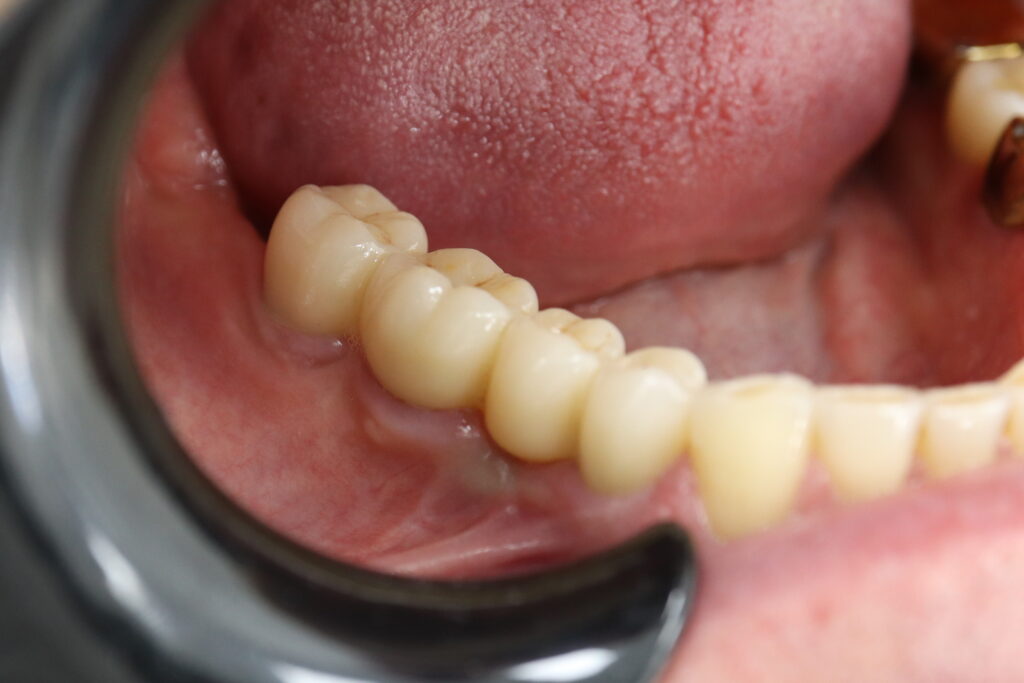

Также на нижнюю челюсть был изготовлен мостовидный протез из 4х коронок (цирконий) с опорой на 3 индивидуальных абатмента с одной стороны и 1 коронка на иплантат с другой.

Спустя 27 дней был зафиксирован протез с опопрой на дентальные имплантаты из диоксида циркония с каркасом из титана.